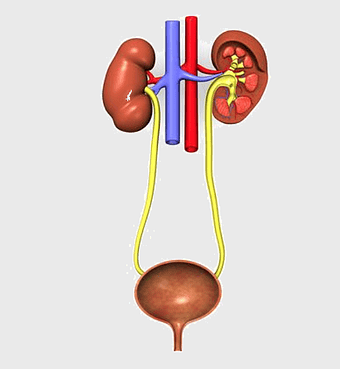

urinary system anatomy, kidney function illustration, ureter diagram, bladder infection symptoms, renal system health, excretory function chart, genitourinary medical diagram -

chronic kidney disease illustration, nephron structure diagram, kidney transplant medical image, excretory system anatomy, renal blood flow visualization, human kidney cross-section, medical education graphics -

kidney anatomy, human kidney illustration, kidney cancer awareness, kidney organ diagram, renal system structure, medical kidney image, urinary system components -

kidney anatomy diagram, human kidney structure, adrenal gland and kidney, kidney stone illustration, renal system diagram, urinary system anatomy, kidney blood vessels -